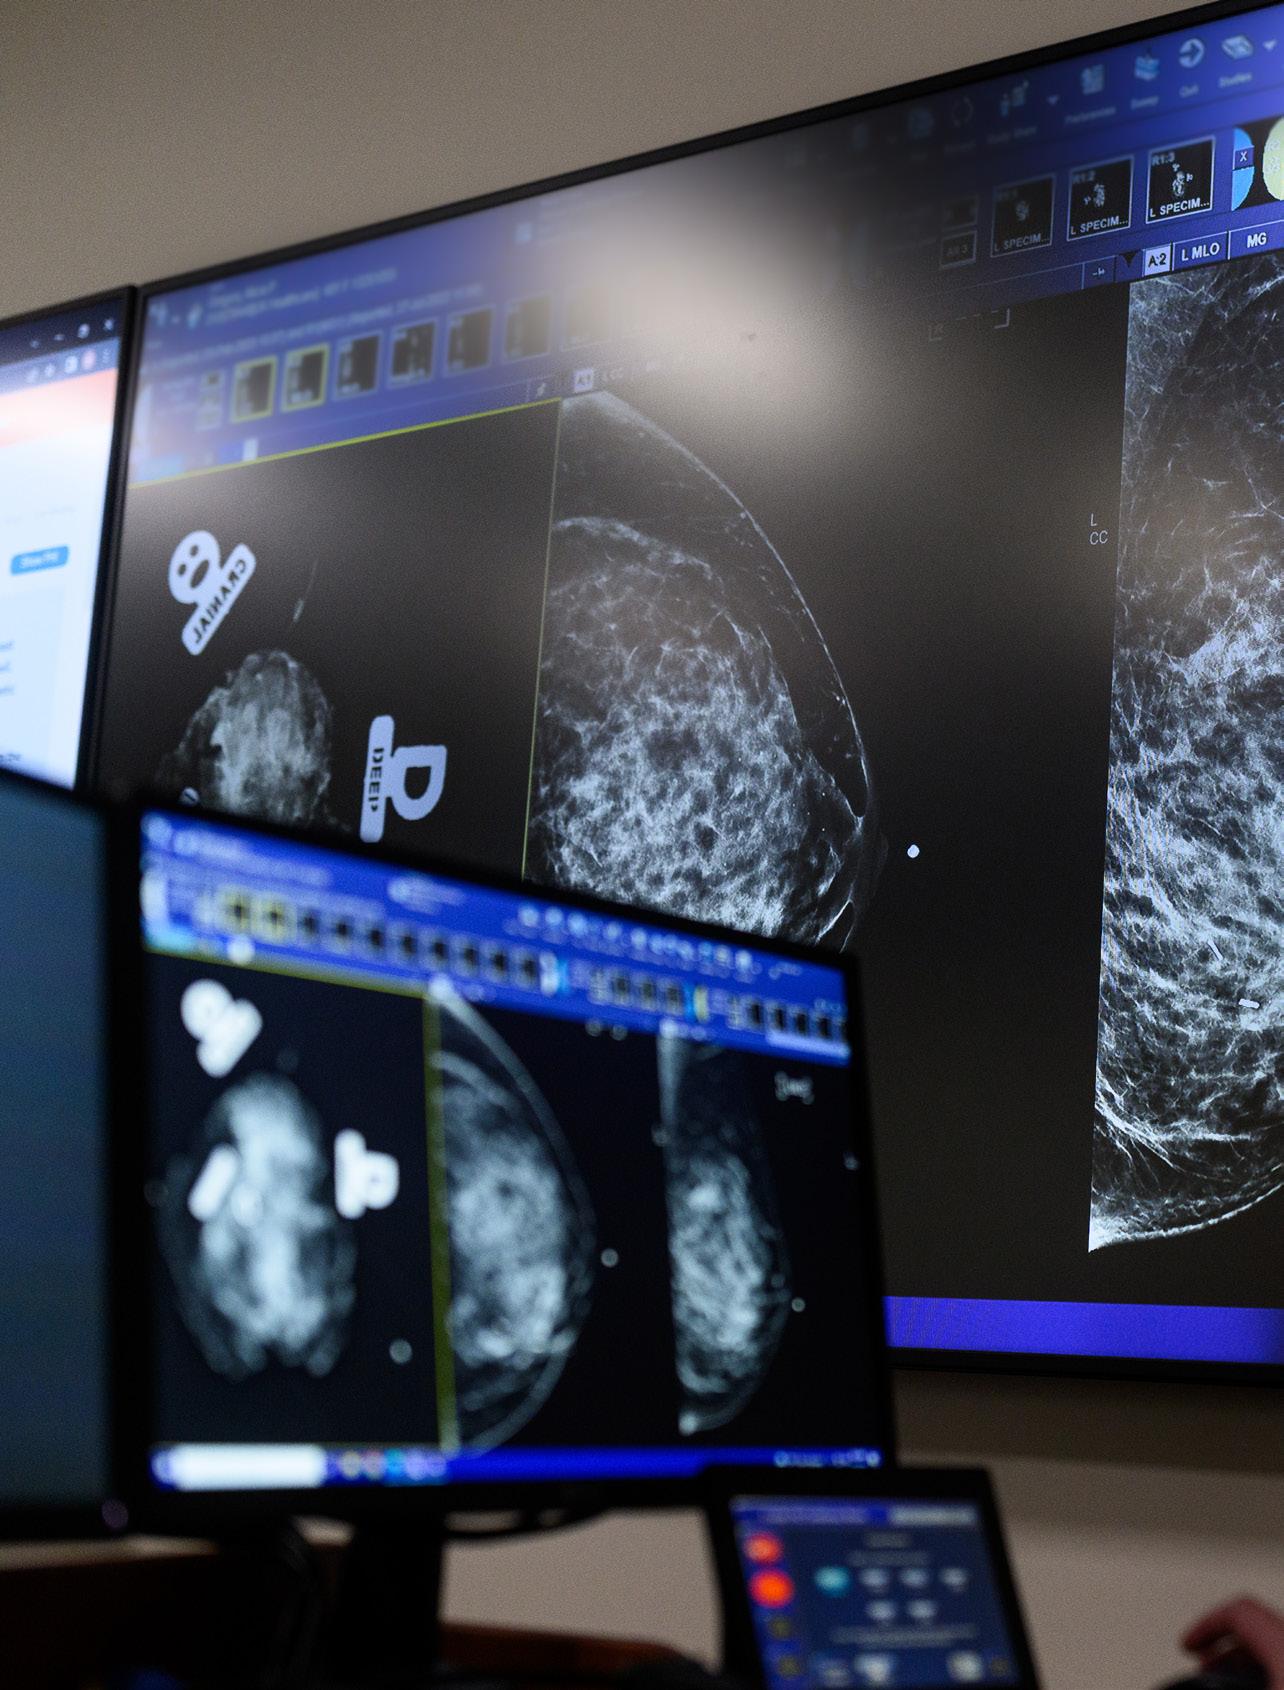

Margaret M. Szabunio, MD, FACR, FAAWR

Full-Time Faculty Complement: 7

• Interpreted diagnostic and screening mammography, MRI, and ultrasound images of breast; performed image-guided procedures of breast in adults

• Participated in multiple weekly multidisciplinary clinical care team conferences

• Continued to provide on-site and teleradiological coverage for community radiology professional services contracts with HCA/Frankfort Regional Medical Center, Primary Care Centers of Eastern Kentucky, and Rockcastle Regional Hospital and Respiratory Care Center Breast Radiology